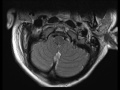

Retroclival Hematoma

12-year-old male struck by a motor vehicle while riding a bike. On the sagittal STIR-weighted off midline image, there is asymmetric widening of the atlanto-occipital interval with slight anterior translocation of the occipital condyle to the atlas with an associated effusion. The more midline T2 and T1-weighted sagittal and axial images at the level of the craniocervical junction demonstrate avulsion and elevation of the tectorial membrane from the clivus by an underlying hematoma. There is extensive pre vertebral soft tissue edema from the craniocervical junction to the level of the superior endplate of vertebra C4. This is a case of a retroclival hematoma in the setting of a craniocervial dissociation. Craniocervical junction injuries are up to 10x more common in first decade of life as compared to older children and adults. Neurologic status at the time of presentation is the best predictor of outcome.